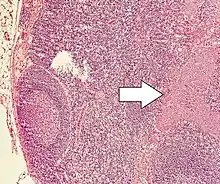

| Micrograph of a neuroendocrine tumor. H&E stain | |

NETs are often small, yellow or tan masses, often located in the submucosa or more deeply intramurally, and they can be very firm due to an accompanying intense desmoplastic reaction. The overlying mucosa may be either intact or ulcerated. Some GEP-NETs invade deeply to involve the mesentery.[69] Histologically, NETs are an example of "small blue cell tumors," showing uniform cells which have a round to oval stippled nucleus and scant, pink granular cytoplasm. The cells may align variously in islands, glands or sheets. High power examination shows bland cytopathology. Electron microscopy can identify secretory granules. There is usually minimal pleomorphism but less commonly there can be anaplasia, mitotic activity, and necrosis.